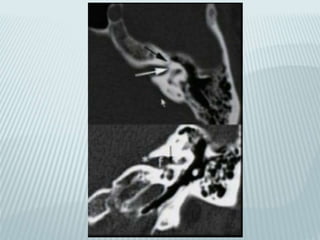

Posterior petrous aqueducts

Vestibular (endolymphatic):

parallel to petrous ridge

Cochlear (perilymphatic):

Verticaly below and parallel to

inner ear canal

VESTIBULAR AQUEDUCT

 10 mm long endolymphatic duct

 From common crus to post wall of petrous

pyramid

 Joins endolymphatic sac nestled in leaves of

dura

 Equilibration of endolymphatic fluid pressure

 subdural

COCHLEAR AQUEDUCT

 8 mm long perilymphatic aqueduct

 From basal turn of cochlea to medial border

of jugular foramen

 Regulation of CSF and perilymphatic fluid

pressure

 Subarachnoid